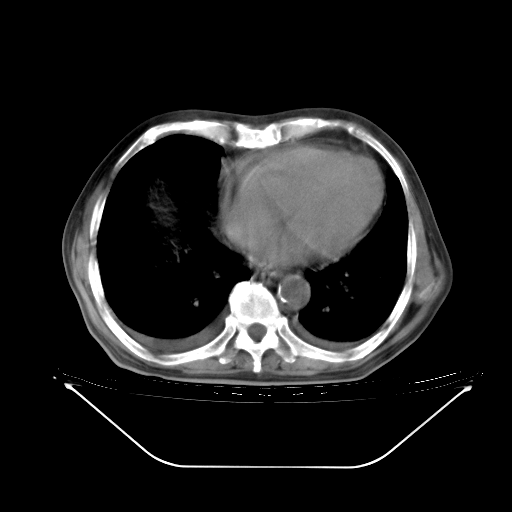

今天复查肺部CT,发现双肺广泛磨玻璃样改变。所以我把3月19日和5月9日相隔50天的肺部CT上传。请大家会诊。

5月9日肺部CT(在4月27日齐鲁医院肺部CT描述部分肺组织磨玻璃样改变,12天后肺组织广泛磨玻璃样改变)

2009年5月9日肺部CT

大致读了系列胸部CT:纵隔窗无明显异常,肺窗:从4、27至今:主要是双肺中下野外带可见毛玻璃样改变,目前处于急性肺泡炎阶段,至于原因考虑1、结替组织或胶原血管性疾病所致?2、恶性疾病如恶组在肺部所致的表现或细支气管肺泡癌?3、药物或其它原因如肺蛋白沉着症所致肺泡炎目前不太可能?总之,明天就去请我院的呼吸科、感染科、血液科和临免专家会诊哈。